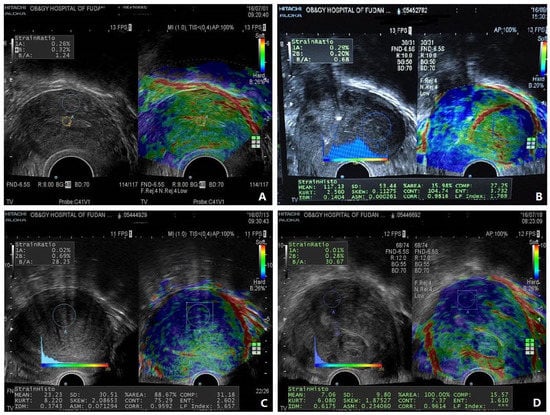

- Liu, X.; Ding, D.; Ren, Y.; Guo, S.W. Transvaginal Elastosonography as an Imaging Technique for Diagnosing Adenomyosis. Reprod. Sci. 2018, 25, 498–514. [Google Scholar] [CrossRef]

- Stoelinga, B.; Hehenkamp, W.J.; Brolmann, H.A.; Huirne, J.A. Real-time elastography for assessment of uterine disorders. Ultrasound Obs. Gynecol. 2014, 43, 218–226. [Google Scholar] [CrossRef]

- Stoelinga, B.; Hehenkamp, W.J.K.; Nieuwenhuis, L.L.; Conijn, M.M.A.; van Waesberghe, J.; Brolmann, H.A.M.; Huirne, J.A.F. Accuracy and Reproducibility of Sonoelastography for the Assessment of Fibroids and Adenomyosis, with Magnetic Resonance Imaging as Reference Standard. Ultrasound Med. Biol. 2018, 44, 1654–1663. [Google Scholar] [CrossRef]

- Sasaran, V.; Turdean, S.; Marginean, C.; Gliga, M.; Ilyes, L.; Grama, O.; Puscasiu, L. Transvaginal Ultrasound Combined with Strain-Ratio Elastography for the Concomitant Diagnosis of Uterine Fibroids and Adenomyosis: A Pilot Study. J. Clin. Med. 2022, 11, 3757. [Google Scholar] [CrossRef]

- Sasaran, V.; Turdean, S.; Gliga, M.; Ilyes, L.; Grama, O.; Muntean, M.; Puscasiu, L. Value of Strain-Ratio Elastography in the Diagnosis and Differentiation of Uterine Fibroids and Adenomyosis. J. Pers. Med. 2021, 11, 824. [Google Scholar] [CrossRef] [PubMed]